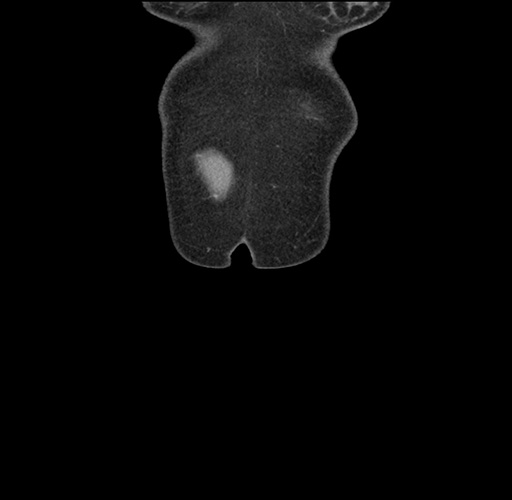

Imaging Analysis

Look through the patient's CT scan to identify any areas of concern for the necessary procedure.

Based on your CT findings, which issue(s) would give reason for "planned slowing down moment(s)" in this case?

Considering a standard left lateral sectionectomy procedure, what step(s) of the operation would you do differently in this case ?